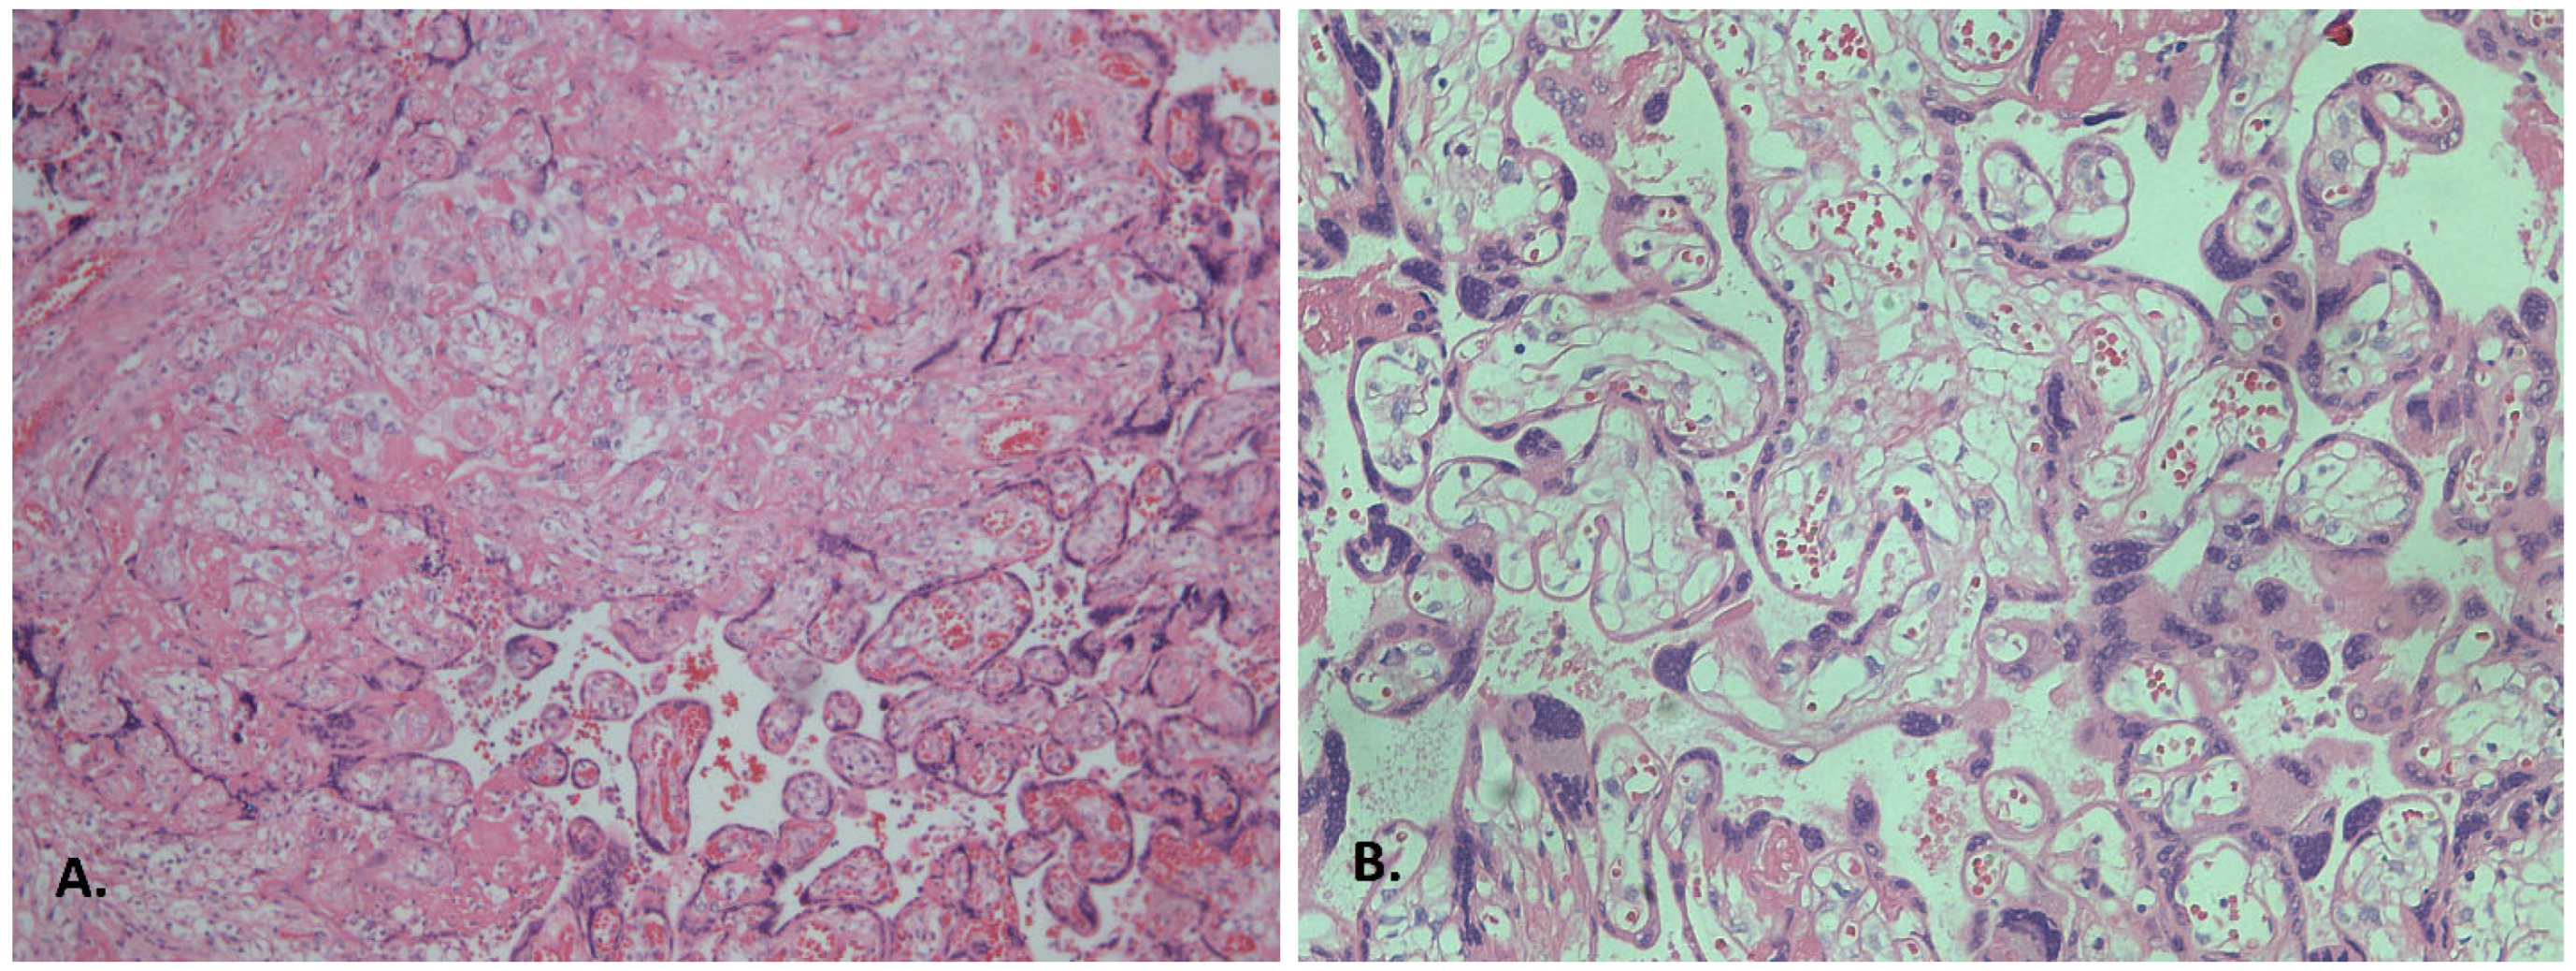

3.2. Histological Findings

3.2.1. Inflammatory Alterations

3.2.2. The Influence of Clinical Manifestations of COVID-19 on the Severity of Morphological Changes in the Placenta

3.2.3. Analysis of the Influence of Clinical Manifestations of COVID-19 on the Severity of Fetal Vascular Lesions